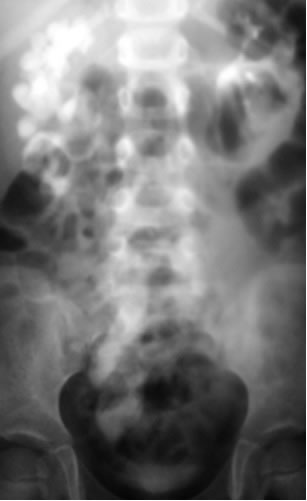

Необструктивная форма:

Приведены данные при уретероманометрическом исследовании.

При этом отмечается значительное снижение внутримочеточникого

давления и отсутствие сокращений мочеточника при необструктивной

форме мегауретера.